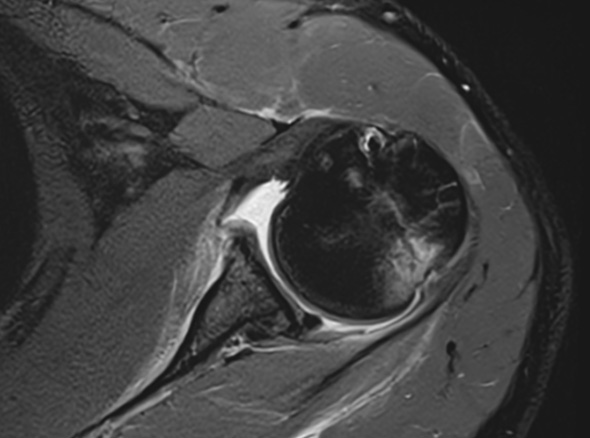

관절 내시경을 통해 늘어나 있는 관절낭을 알맞은 긴장도를 갖도록 봉합하여 줍니다.

이러한 경우

관절낭 중첩술을

고려합니다.

다방향성 불안정증